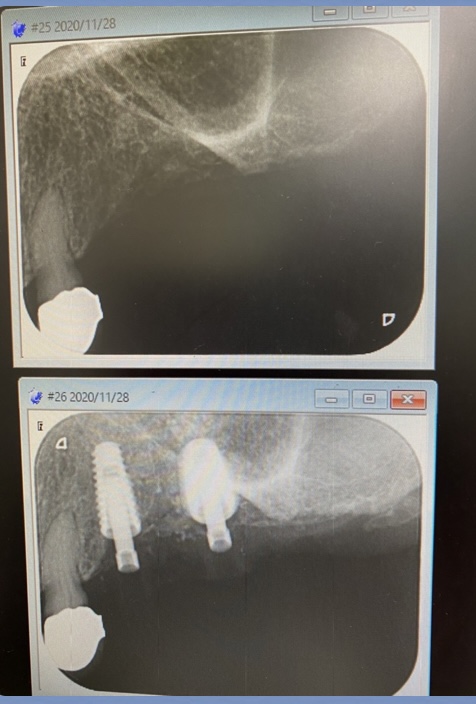

2症例共にソケットリフト法を併用するオペです。

午後の方は、洞底皮質骨に絡み値も良く即時荷重非接触の仮歯まで装着しました。

(オペ後、仮歯装着まで)